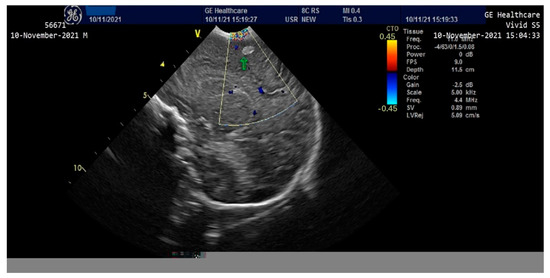

The newborn exhibited hepatomegaly with the right lobe extending caudally. Enlarged hepatic vein and associated splenomegaly were observed on abdominal ultrasound. A cardiac ultrasound revealed mild pulmonary hypertension, mild sized patent ductus arteriosus with left to right shunt, patent foramen ovale with left to right shunt, representing mild cardiac involvement which responded accordingly to the inotrope and vasopressors agents.

The newborn was admitted to the NICU with an extremely severe condition, pale skin, generalized edema with the appearance of hydrops, generalized purpura, ecchymosis of the cephalic extremity, parietooccipital cephalohematoma, abdomen with important wall edema and ascites fluid. Thoracoabdominal radiography and abdominal ultrasound showed the presence of ascites fluid and poor aeration of the colic frame (Figure 2).

Figure 2.

Thoraco-abdominal X-ray-poor aeration of the colic frame, ascites fluid.